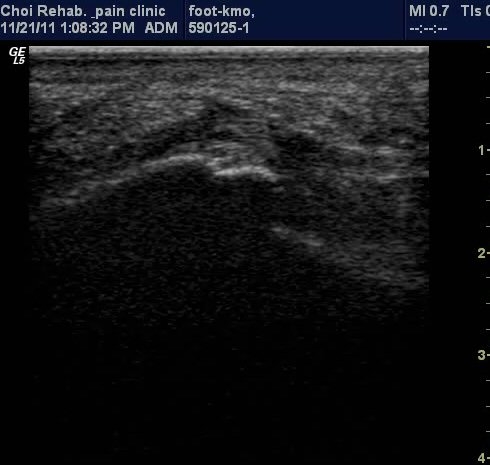

µÚ²ÞÄ¡ Á¾´Ü¸é°Ë»ç¿¡¼­ Á·Àú±Ù¸·ÀÇ Àú¿¡ÄÚ ºÎÁ¾ÀÌ ¶Ñ·ÈÇÔ(±×¸² 1, 2).